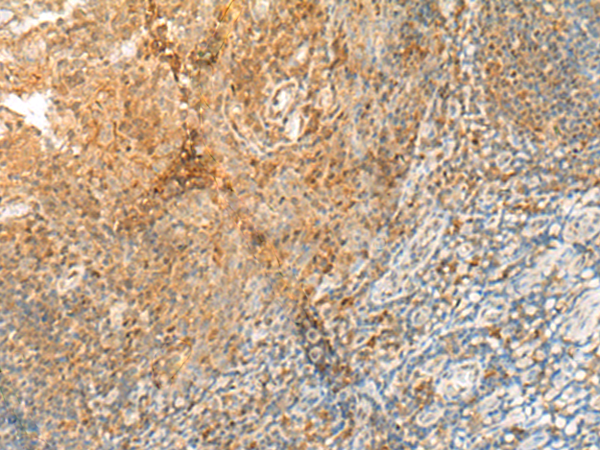

分类: 科研抗体货号: P13552别名:应用: IHC反应种属: Human